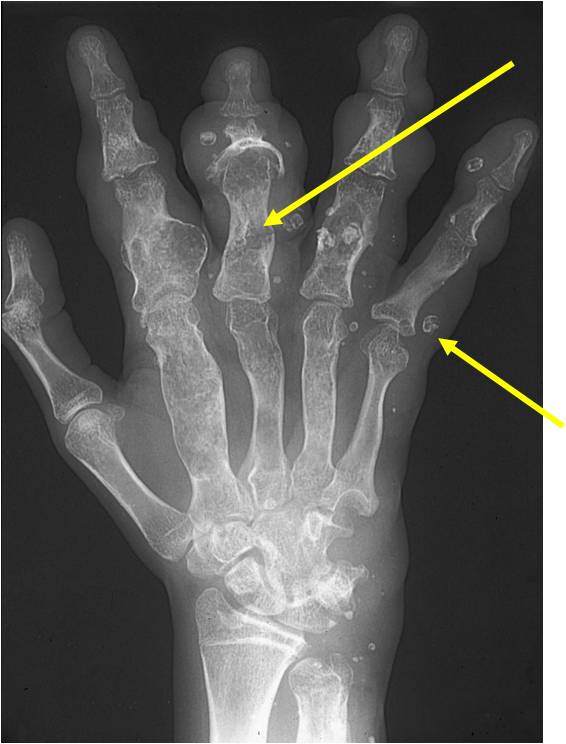

- 50% involve hands and feet (mostly phalanges)

- Localized, radiolucent defect usually with punctate calcifications

- Calcifications are typical but not always present

- Matrix may demonstrate various degrees of calcification

- Calcifications are stippled, punctate, popcorn like calcifications and “Ring and Arc” calcifications

- Cortex may be scalloped and thinned in the phalanges

- Geographic lytic lesion

- Central often metaphyseal in long bones

- Expansile remodeling with thinned cortex

- Chondroid matrix with calcifications in majority of tumors

- Approximately 20% have limited or no calcifications

- Phleboliths (calcifications) usually seen in hemangiomas on X-ray